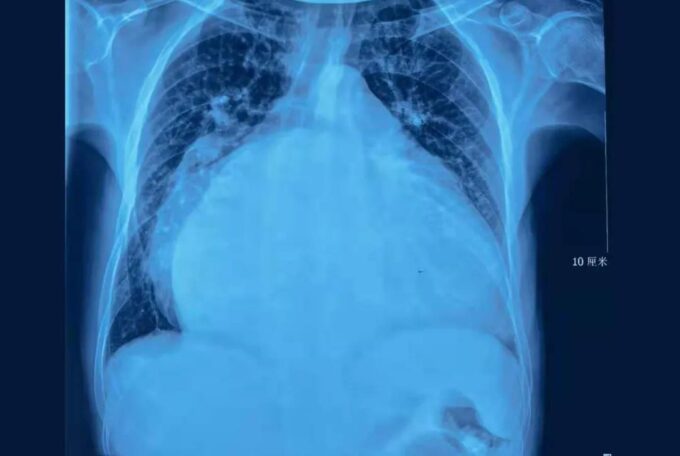

50岁男子心脏直径接近20厘米,状如篮球塞满整个胸腔,严重挤压双肺等脏器,心功能严重受损随时都有生命危险……

患者病情严重,当地医院无法救治,建议转到阜外华中心血管病医院。心外科权晓强主任医师接诊后,完善相关检查,当他拿到李先生的胸片后,简直不敢相信自己的眼睛:整个胸腔,全是心脏!

“这就是‘篮球心’,心功能很差,必须尽快手术!”权晓强主任医师说道。可是,要想手术谈何容易,患者的心脏问题太复杂,不但有瓣膜问题、心律失常问题,还有重度肺动脉高压,这一项可是手术的禁忌症。以李先生这样的瓣膜病,外科手术是最佳治疗选择。但当时患者已经发展成了肺动脉高压,手术的话风险很大,不手术的话,眼看患者就要撑不下去。看着患者求生的眼神,权晓强主任医师决定发挥医院多学科优势,充分利用自己留学回国的经验积累,做好术前相关准备,拼尽全力把手术做好,为患者争取一线生机。